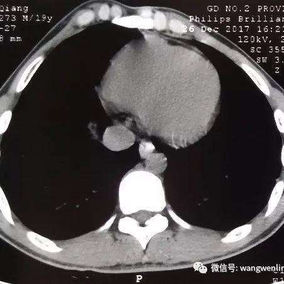

Preoperative Examination

The chest wall exhibits a large area of prominent and bilaterally symmetrical protrusion, predominantly in the upper half. There are also mild depressions on both sides of the lower half of the chest wall.